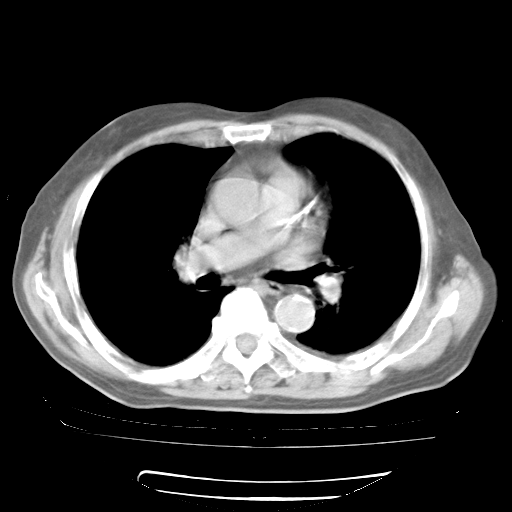

4月28日肺部CT

1、108#的是4月14日的胸部CT(发此贴时还没看着28日的CT)。14日的胸部CT其实已经出现改变(如108#所述),个人认为28日的胸部CT除纵膈窗疑似有双侧胸膜增厚或少量胸积液(可行胸部B超明确)外,与4月14日对照病变有所加重;2、已经给予“异烟肼、利福平、乙胺丁醇”抗痨治疗?如果是,甲强龙80mg可缓慢减量;如果环磷酰胺已停用,暂不使用;3、中性粒细胞92%,明显升高,目前体温情况?注意合并细菌感染可能,使用左氧氟沙星情况下,是否联用B-内酰胺类抗菌药物?另外是查免疫全套非风湿全套。